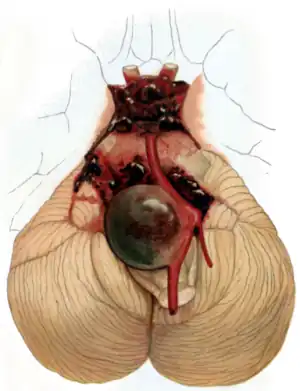

| Aneurysm of the basilar artery and the vertebral arteries. | |

Aneurysms in the posterior circulation (basilar, vertebral and posterior communicating artery) have a higher risk of rupture. Basilar artery aneurysms represent only 3–5% of all intracranial aneurysms but are the most common aneurysms in the posterior circulation.